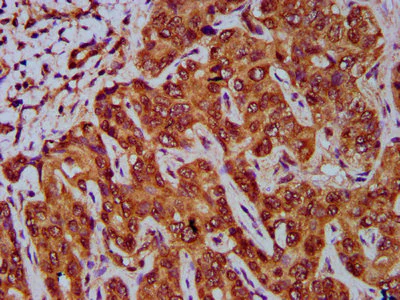

Immunohistochemistry (Formalin/PFA-fixed paraffin-embedded sections) - Anti-GNA12 antibody (AB236617)

Paraffin-embedded human liver cancer tissue stained for GNA12 with ab236617 at a 1/400 dilution in immunohistochemical analysis.

After dewaxing and hydration, antigen retrieval was mediated by high pressure in a citrate buffer (pH 6.0). Section was blocked with 10% normal goat serum 30 minutes at RT. Then primary antibody (1% BSA) was incubated at 4°C overnight. The primary is detected by a biotinylated secondary antibody and visualized using an HRP conjugated SP system.